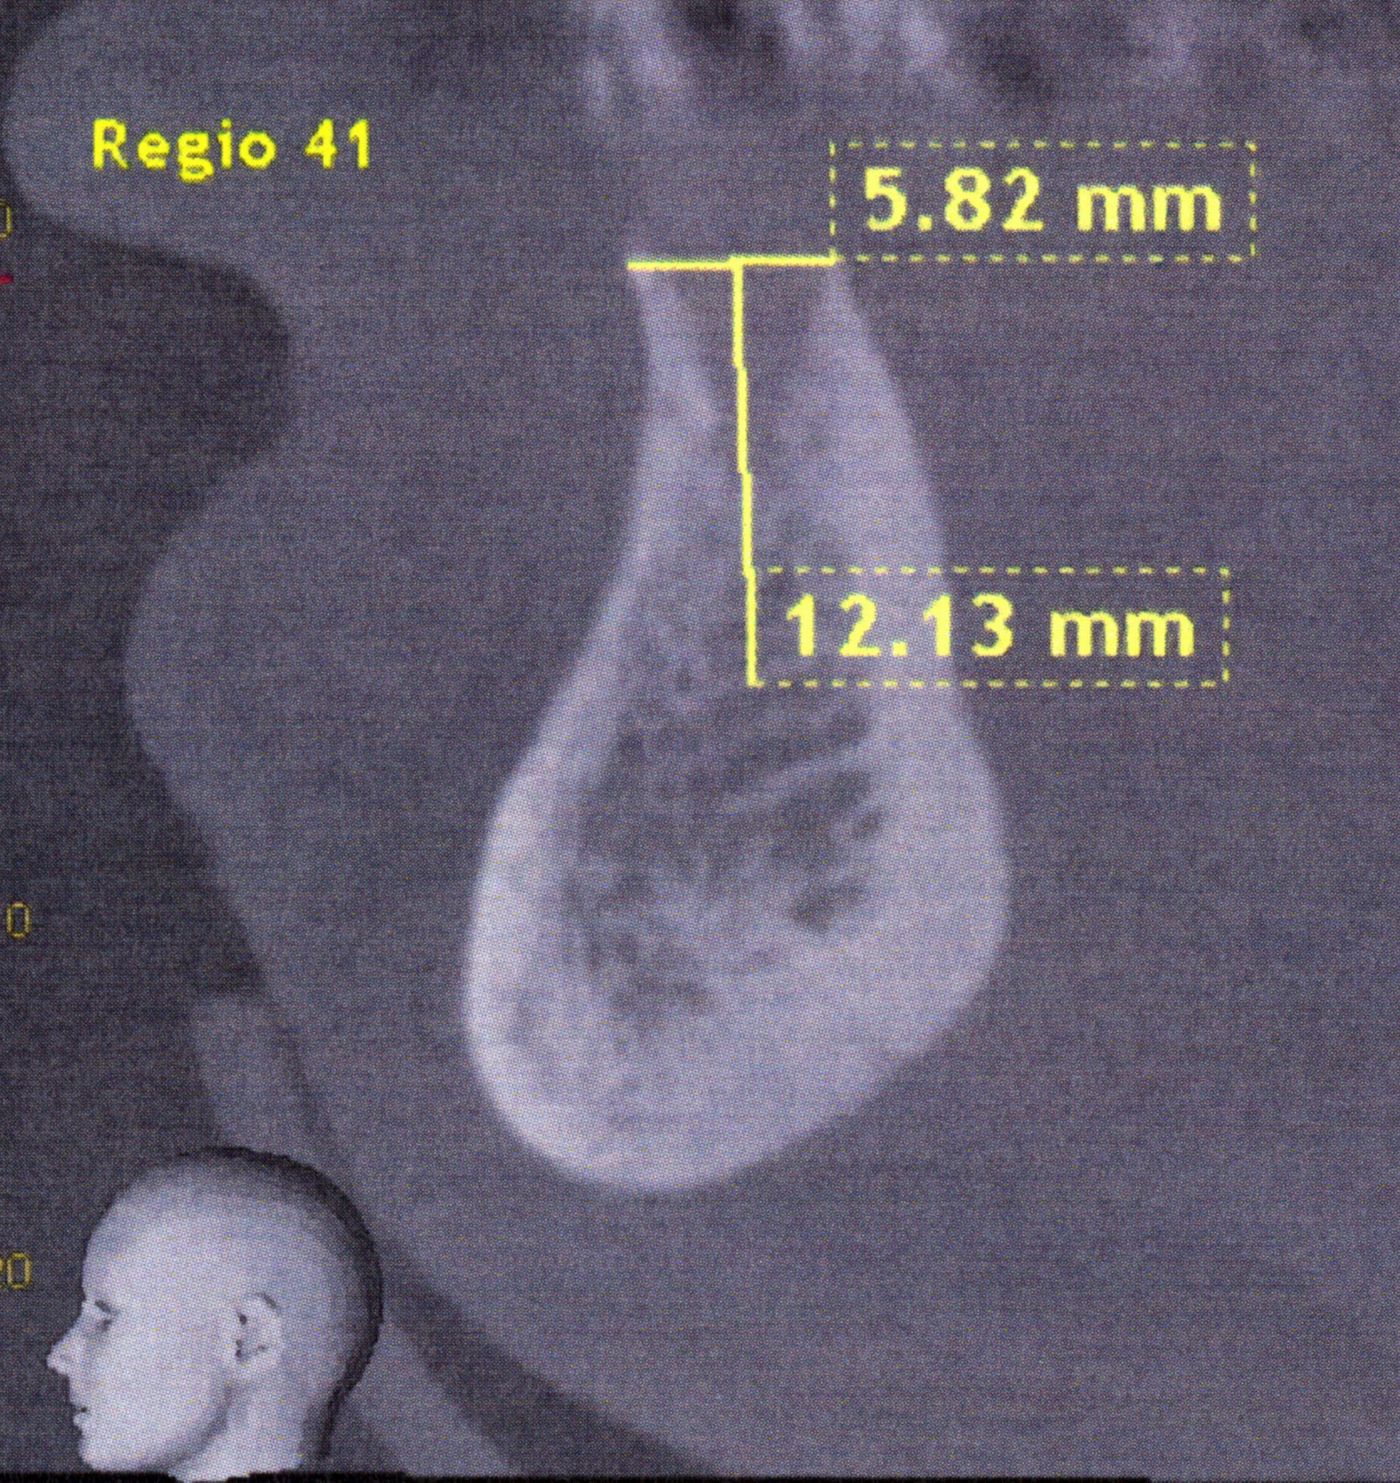

O dente 41 foi extraído, e um escaneamento de CBCT foi registrado nove semanas mais tarde. A avaliação radiográfica revelou uma quantidade adequada de osso nas dimensões vertical e horizontal (Figs. 2, 3). Por causa do espaço estreito na dimensão mésio-distal (Fig. 4), um implante Bone Level Tapered (BLT) com diâmetro reduzido de 2,9 mm foi selecionado para assegurar a limpeza adequada dos espaços interdentais.